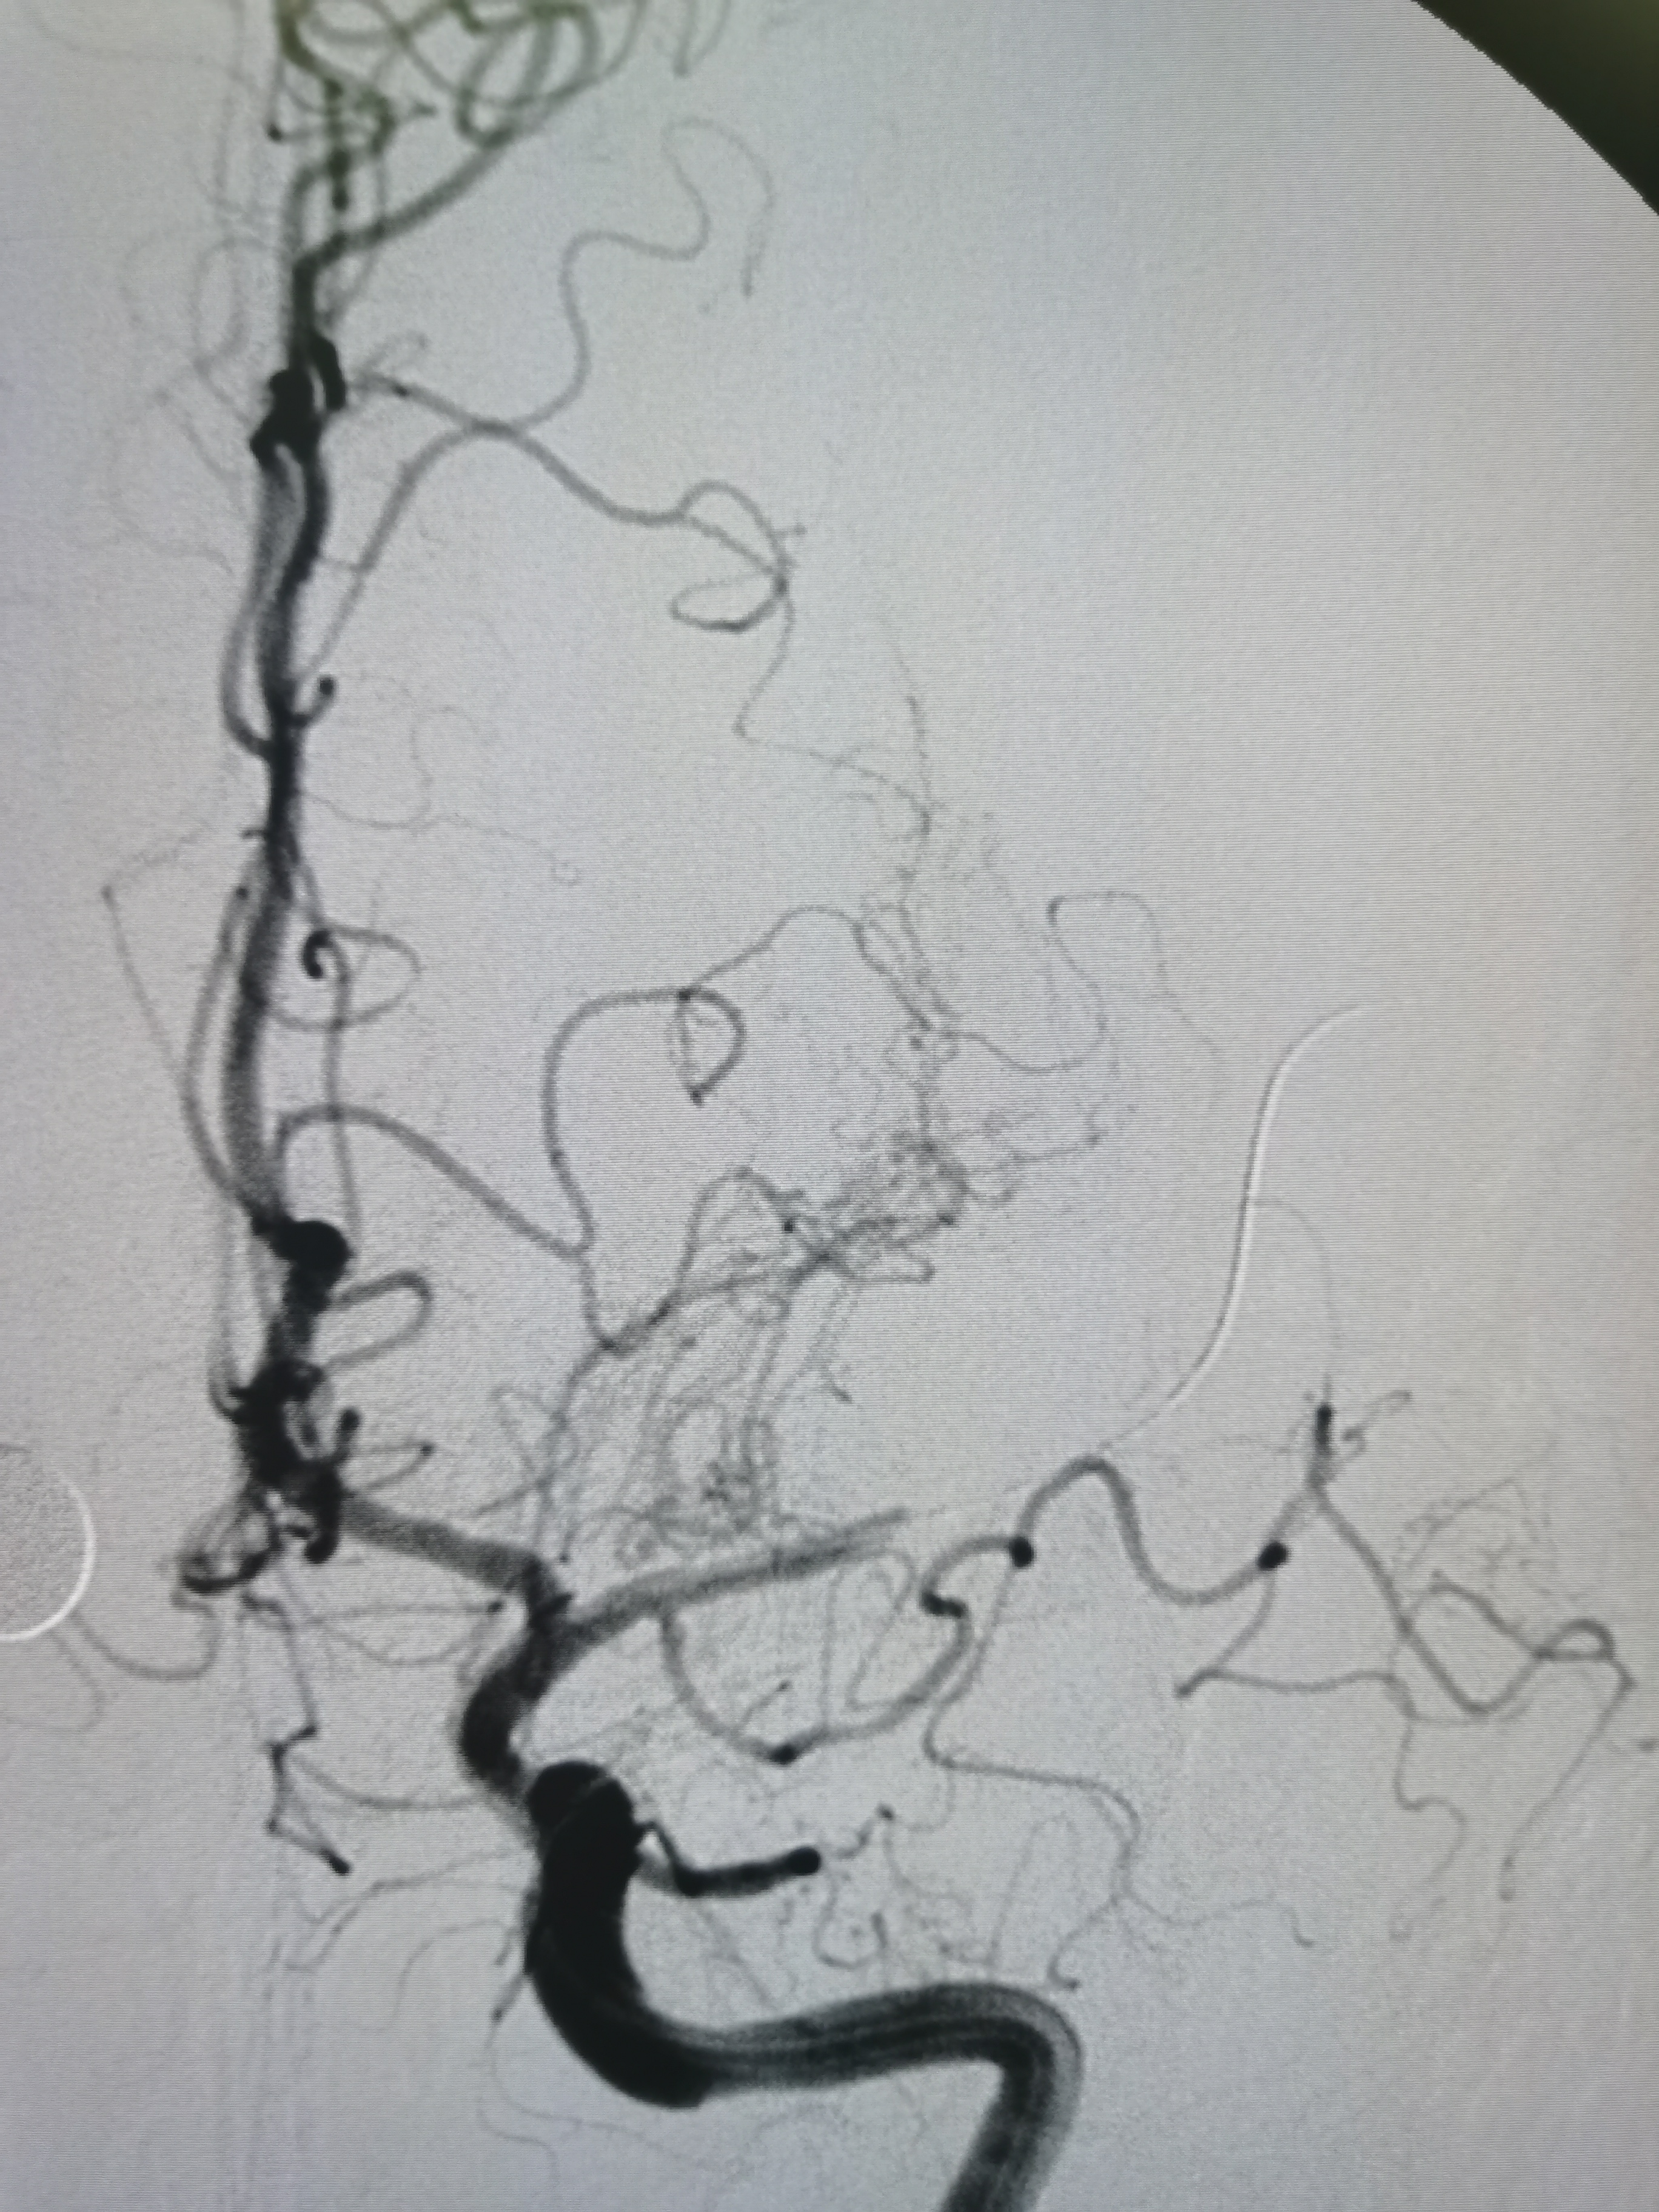

扩张后造影见血管再通,血流通畅。

侧位造影见血流通畅。

观察15分钟后造影血流通畅,未见夹层及明显弹性回缩。

复查造影见颅内狭窄解除,血流通畅,遂未再植入支架,撤出导丝及各级系统,结束手术。患者麻醉苏醒顺利,无新发神经系统症状,给予替罗非班持续泵入,监测生命体征,控制血压避免再灌注损伤。

1、本例患者系因左侧大脑中动脉急性闭塞出现左侧半球梗死,系责任血管。

2、造影评估见左侧大脑中动脉起始段闭塞,但动脉晚期可见远端血管返流显影,考虑闭塞段较短,且为新近闭塞,具备介入治疗指征。

3、球囊扩张后血管狭窄解除,无夹层及弹性回缩,遂未再植入支架,术后继续药物治疗,定期随访。